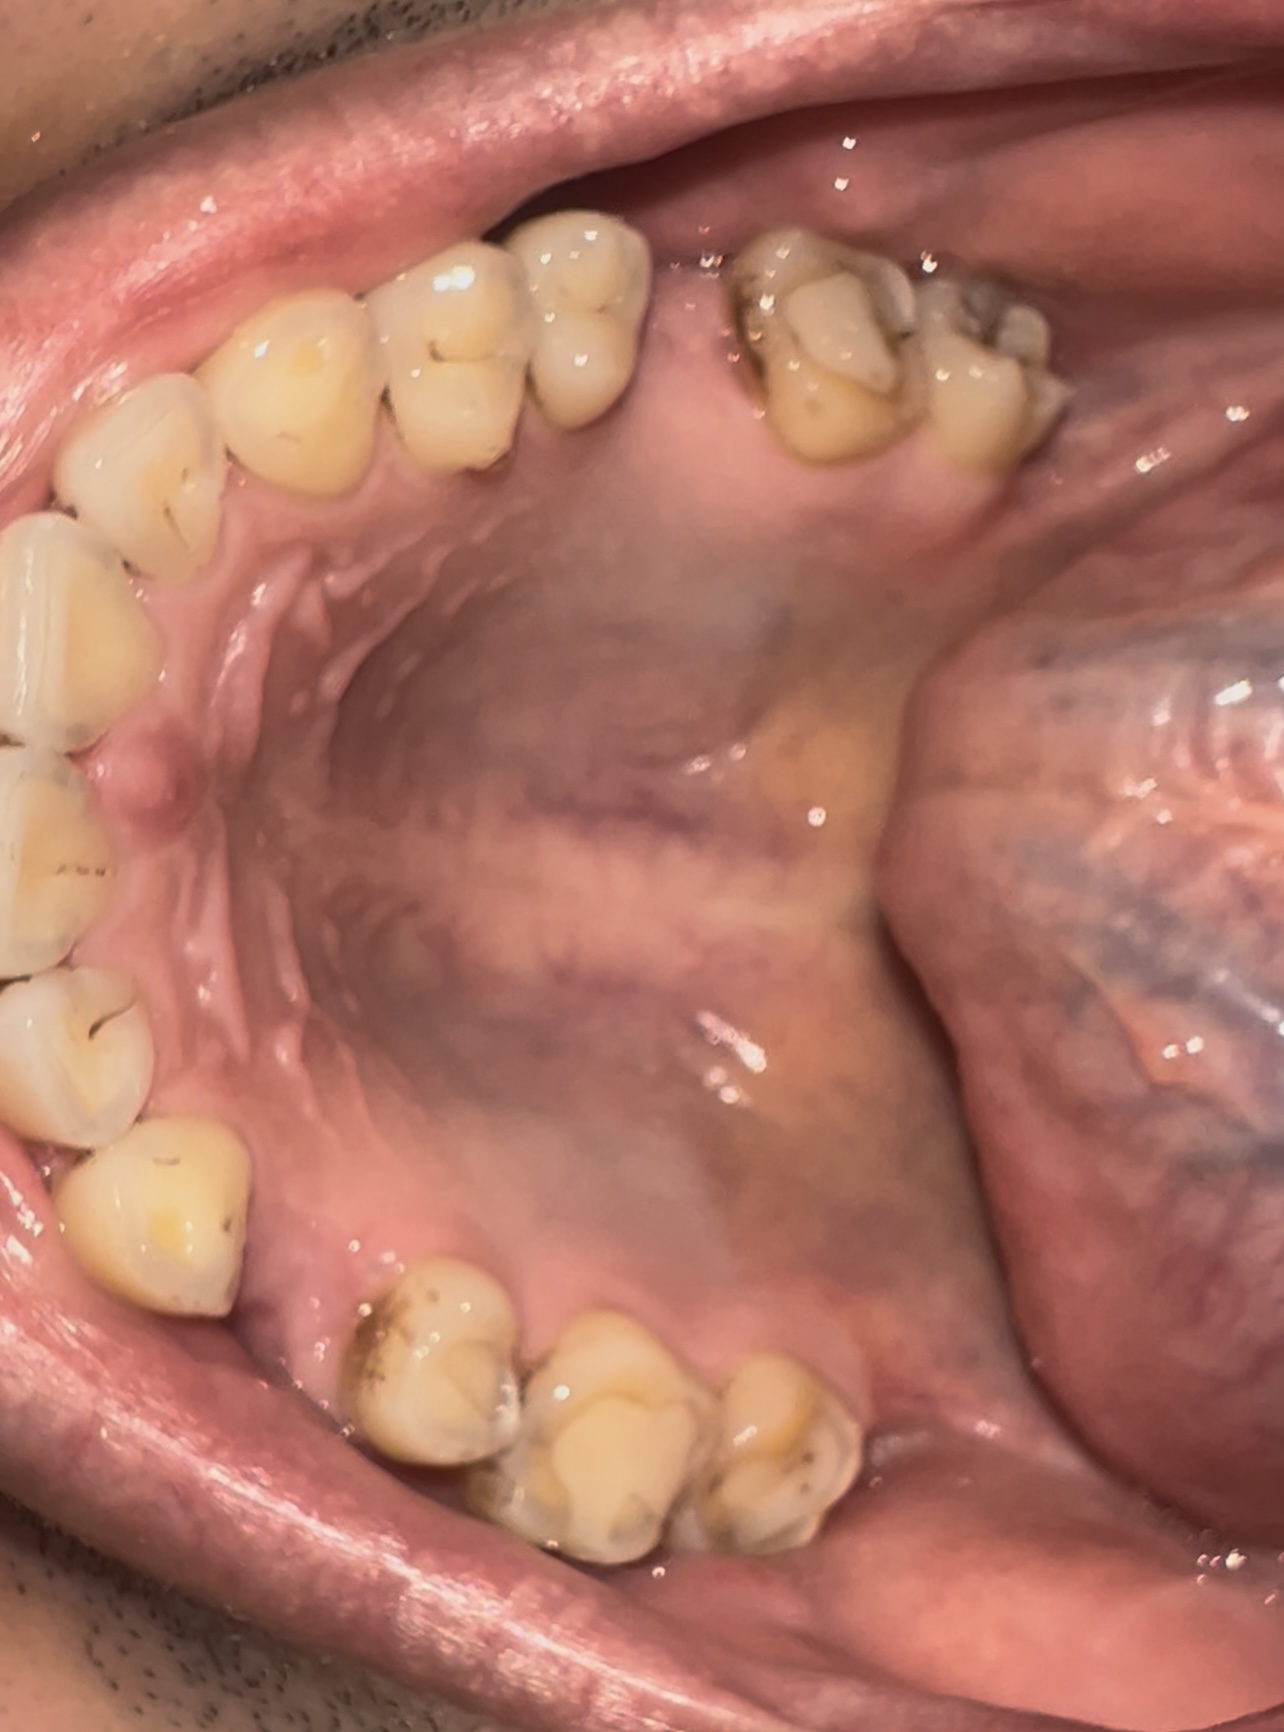

2323.jpg 238Кб, 1412x2047

1412x2047

Аноны, добрый вечер.

Посоветуйте пасту зубную после пломбирования и чистки от камня передних зубов.

Спасибо.

Аноним 06/08/25 Срд 05:38:29 1634925 25

Ска, весь рот в гное, будто бы стоматит, сходил к зубным феям - сказали все збс с корнями зубов и ни одного намёка на кариес где-либо, хотя начиналось всё будто бы флюс и самый пиздец около одного зуба, прописали онли антибиотики, но самое очко , что болезненность ещё и в области мягких тканей подбородка, который и отдает в этот самый пиздец при надавливании - даже будто бы второй подбородок чуть-чуть присутствует, температура и общая слабость, есть риск флегмоны? пиздец за шо(

Аноним 06/08/25 Срд 10:08:53 1634947 26

Как профиль лица меняется после удаления восьмерок? В инете нашел только фотки до/после у женщин, и вроде как челюга уменьшается. У мужиков так же? После удаления не получится больше моггать челюхой омежек?

Аноним 07/08/25 Чтв 13:36:06 1635134 27

>>1634947

>Как профиль лица меняется после удаления восьмерок